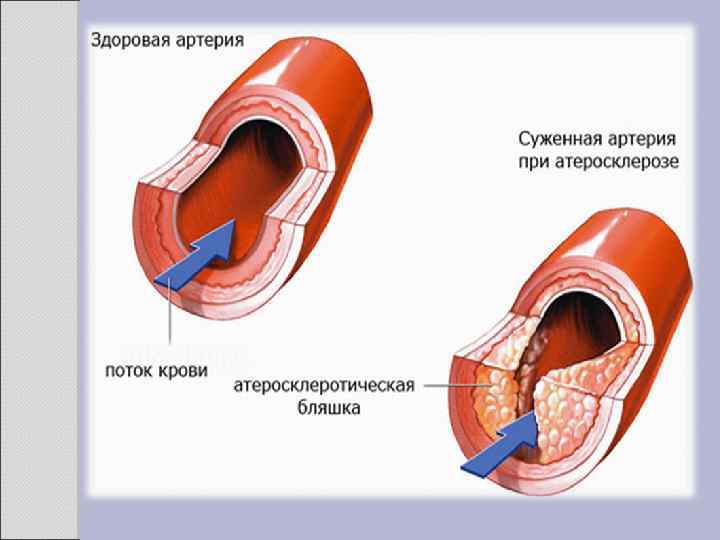

2. 1 АТЕРОСКЛЕРОЗ Атеросклероз — хроническое заболевание эластического и мышечно-эластического типа, возникающее вследствие нарушения липидного обмена и сопровождающееся отложением холестерина и некоторых фракций липопротеидов в интиме сосудов. Отложения формируются в виде атероматозных бляшек. Последующее разрастание в них соединительной ткани (склероз), и кальциноз стенки сосуда приводят к деформации и сужению просвета вплоть до облитерации (закупорки). Этиология На данный момент единой теории возникновения данного заболевания нет. Выдвигаются следующие варианты, а также их сочетания: • теория липопротеидной инфильтрации — первично накопление липопротеидов в сосудистой стенке, • теория дисфункции эндотелия — первично нарушение защитных свойств эндотелия и его медиаторов, • аутоиммунная — первично нарушение функции макрофагов и лейкоцитов, инфильтрация ими сосудистой стенки, • моноклональная — первично возникновение патологического клона гладкомышечных клеток, • вирусная — первично вирусное повреждение эндотелия (герпес, цитомегаловирус и др. ), • перекисная — первично нарушение антиоксидантной системы, • генетическая — первичен наследственный дефект сосудистой стенки, • хламидиозная — первичное поражение сосудистой стенки хламидиями, в основном, Chlamydiapneumoniae. • гормональная — возрастное повышение уровня гонадотропных и адренокортикотропных гормонов приводит к повышенному синтезу строительного материала для гормонов-холестерина.

Клиника Клинические проявления часто не соответствуют морфологии. При патологоанатомическом вскрытии обширное и выраженное атеросклеротическое поражение сосудов может оказаться находкой. И наоборот, клиника ишемии органа может появляться при умеренной облитерации просвета сосуда. Характерно преимущественное поражение определенных артериальных бассейнов. От этого зависит и клиническая картина заболевания. Поражение коронарных артерий постепенно приводит к коронарной недостаточности, проявляющейся ишемической болезнью сердца. Заинтересованность церебральных артерий вызывает либо преходящую ишемию мозга либо инсульты. Поражение артерий конечностей — причина перемежающейся хромоты и сухой гангрены. Атеросклероз брыжеечных артерий ведет к ишемии и инфаркту кишечника (мезентериальный тромбоз). Также возможно поражение почечных артерий с формированием почки Голдблатта. Даже в пределах отдельных артериальных бассейнов характерны очаговые поражения — с вовлечением типичных участков и сохранностью соседних. Так, в сосудах сердца окклюзия наиболее часто возникает в проксимальном отделе передней межжелудочковой ветви левой коронарной артерии. Другая типичная локализация — проксимальный отдел почечной артерии и бифуркация сонной артерии. Некоторые артерии, например внутренняя грудная, поражаются редко, несмотря на близость к коронарным артериям и по расположению, и по строению. Атеросклеретические бляшки часто возникают в бифуркации артерий — там, где кровоток неравномерен; иными словами, в расположении бляшек играет роль локальная гемодинамика (см. патогенез).